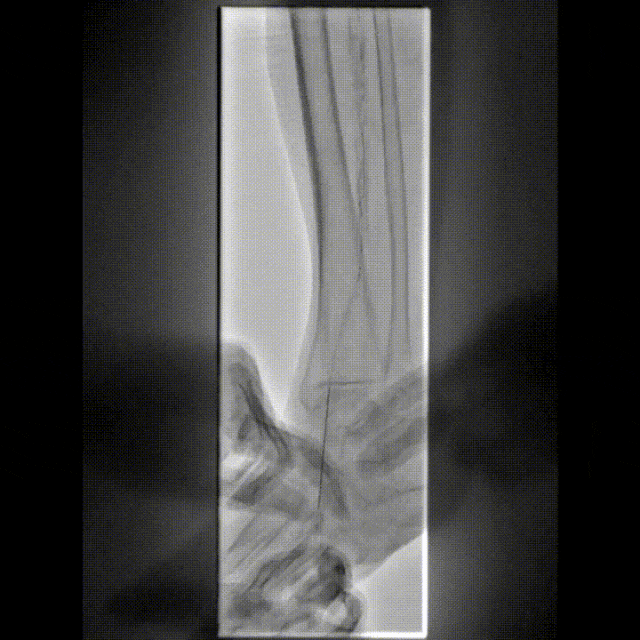

图为:术后造影

术后用药和随访

术后足背动脉搏动好